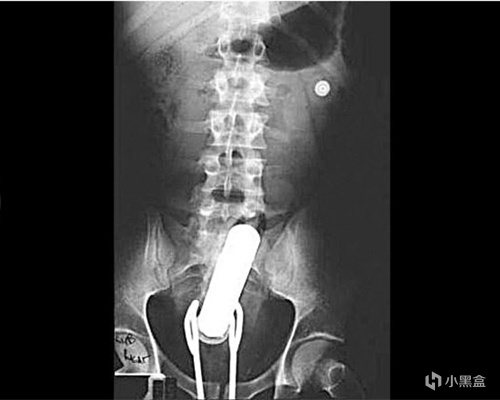

上面有我接診過的患者,也有來源網絡的圖片。但是這種誤入體內的異物,可能有電子產品或者瓶子,甚至也有活物進入的情況。大多數直腸異物發生sex的過程中,被取出的異物包括但不限於按摩棒,橡膠聖劍、高爾夫球、白熾燈等等(也經常有毒販通過包裝好的袋裝毒品藏入胃裏或者直腸裏來販毒)。有一些異物可能一開始已經被完全容納進去,深入體內後難以取出。

比如這位患者在嘗試用夾鉗自救取出異物,可惜一起折戟在體內了不得已就診。

直腸異物典型症狀就是排便困難、腹痛、便血,甚至腸梗阻。如果嘗試自救,反覆磨蹭還可能導致肛管、直腸部分的黏膜水腫和肌肉痙攣,進而更難取出異物。而且最好不要輕易嘗試在不確定異物種類和位置的情況下,做直腸檢查。要不然容易導致異物破裂,造成二次傷害。

一般在直腸鏡下通過夾鉗和牽引取出位置較低的異物,高位的就需要結腸鏡和手術取出了。總結來說,這屬於人禍導致的,無論是否是自己主動塞進去異物,最後都需要儘早解決。